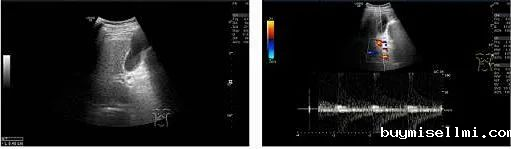

1)超声复查

TIPS术后:

? 支架内血流充填好,支架内峰值流速206cm/s

? 门静脉主干内径12mm,门静脉血流信号充填良好,为单色向肝血流,PSV 72cm/s

? 脾静脉胰腺段内径9mm,PSV 37cm/s,脾门处内径10mm,PSV 36cm/s

? 肠系膜上静脉近汇合处内径9mm,PSV 41cm/s